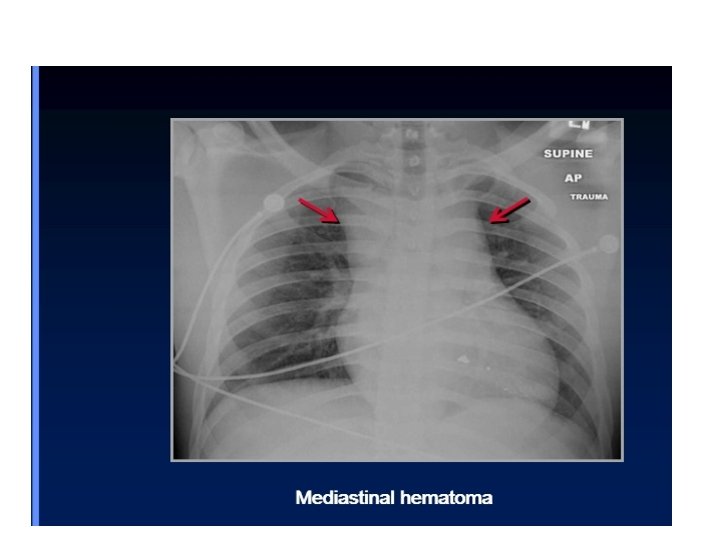

Chest trauma